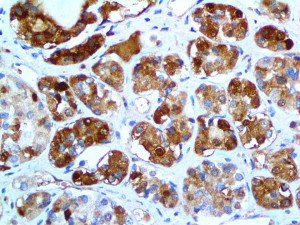

It is the ICU physician who is most likely to witness one of the deadliest manifestations of the abnormal immunological response, the cytokine storm syndrome (CSS). This response is also referred to by some as the cytokine release syndrome (CRS). CSS is characterized by continuous activation and expansion of macrophage and lymphocyte populations, which secrete large amounts of cytokines, causing the cytokine storm. This massive cytokine release is akin to hemophagocytic lymphohistiocytosis (HLH) disease, a syndrome characterized by initial unchecked and persistent activation of cytotoxic T lymphocytes and NK cells.

Clinical and laboratory manifestations of HLH include fever, enlarged liver and/or spleen, neurologic dysfunction, coagulopathy, liver dysfunction, cytopenias (i.e., low levels of erythrocytes, leukocytes, and/or platelets), hypertriglyceridemia, hyperferritinemia, hemophagocytosis, and eventually diminished NK cell activity as the immune system becomes progressively paralyzed. HLH can be familial (primary HLH) or secondary to another disease process (sHLH), such as rheumatic disease, in which it is referred to as macrophage activation syndrome (MAS, characterized by elevated ferritin).